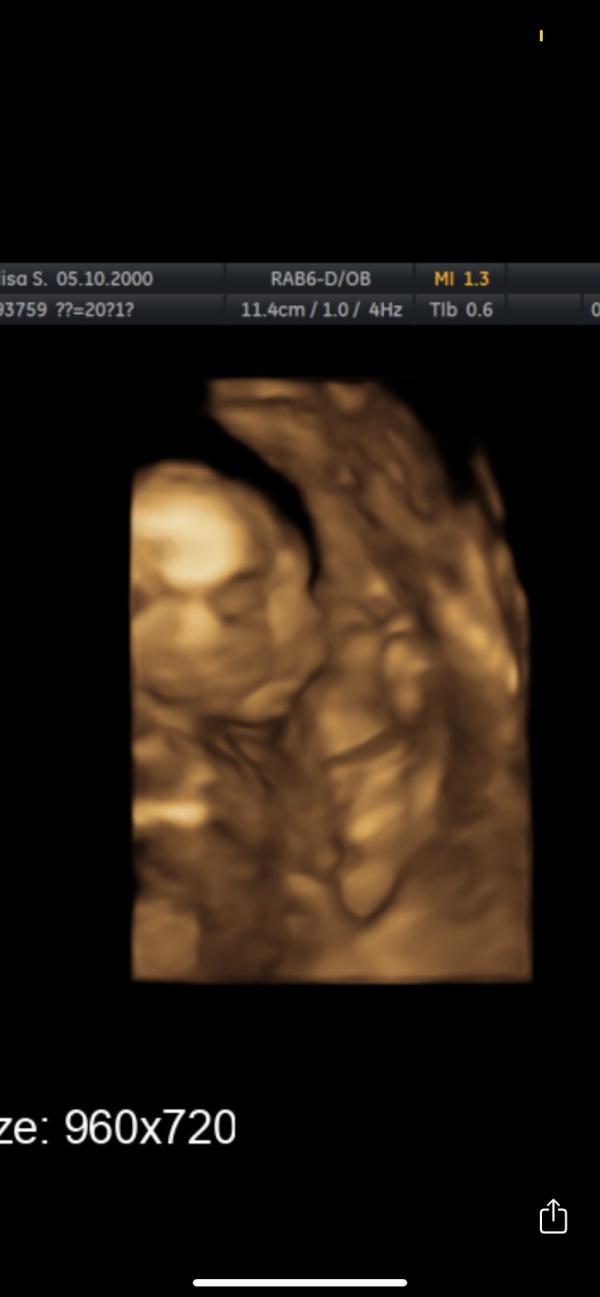

Девочки, на каком сроке лучше идти на 3Д узи?) когда их уже хорошо видно?) вот в 20 недель делала узи, включили 3д, но прям не очень как будто 😅

Хочу повторить попозже)

В 27 уже хорошенький) в 20 у меня был инопланетянин 😅

Вот и у меня инопланетянка 😂😂

Я ходила на 28 очень хорошо видно было)